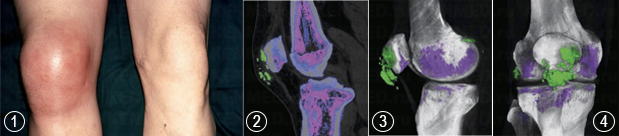

Снимок колена 45-летнего мужчины (1)

Изображение КТ (2) позволяют диагностировать наличие подагрических тофусов, содержащих кристаллы мононатриевого урата (зеленые области)

Трехмерные реконструированные КТ-изображения с цветовой кодировкой, просматриваемые с бокового (3) и фронтального (4) аспектов колена, более точно отображают подагрические тофусы